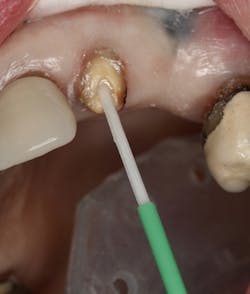

Figure 2: Intaglio surface of existing PFM retrofit preparation

The intaglio surface of the PFM crown contained the preexisting dentin core preparation. The decision was made to prepare the surface to receive the intraoral portion of the post rather than completely remove the remaining dentin (figure 2). This was done to facilitate a smooth retrofit between the remaining root structure and intaglio crown surface as well as to maximize bonding surface area between segments.